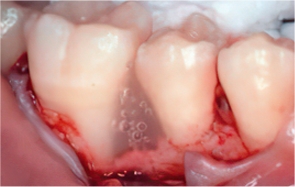

엠도게인 수술과정

잇몸을 절개

STEP 02

Scaling Root Planning을 실시

-

STEP 03

치석 및 치태 등 제거